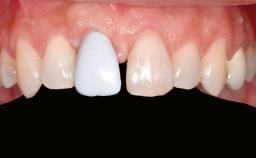

A 47-year-old woman who had suffered from aggressive periodontitis requiring a number of periodontal interventions over more than 10 years was referred by her general dental practitioner and periodontologist for bone augmentation and implant therapy. Her failing dentition had already been scheduled for extraction. The patient expressed a desire for implant-supported fixed restorations and esthetic improvement of her lower face. She had agreed to consult with a maxillofacial surgeon after the referring dentist had suggested bone augmentation. An initial examination by the maxillofacial surgeon revealed mobility of all residual teeth in a patient who was very unhappy with the function of her removable partial dentures. Due to periodontally migrated flaring teeth and loss of occlusal support, the vertical dimension of occlusion was dramatically reduced. The patient was displeased with her lower face because of deepened nasolabial, commissural, and supramental folds.

Patient's Esthetic Expectations Low Medium High

Lip Line No exposure of papillae Exposure of papillae Full exposure of mucosa margin